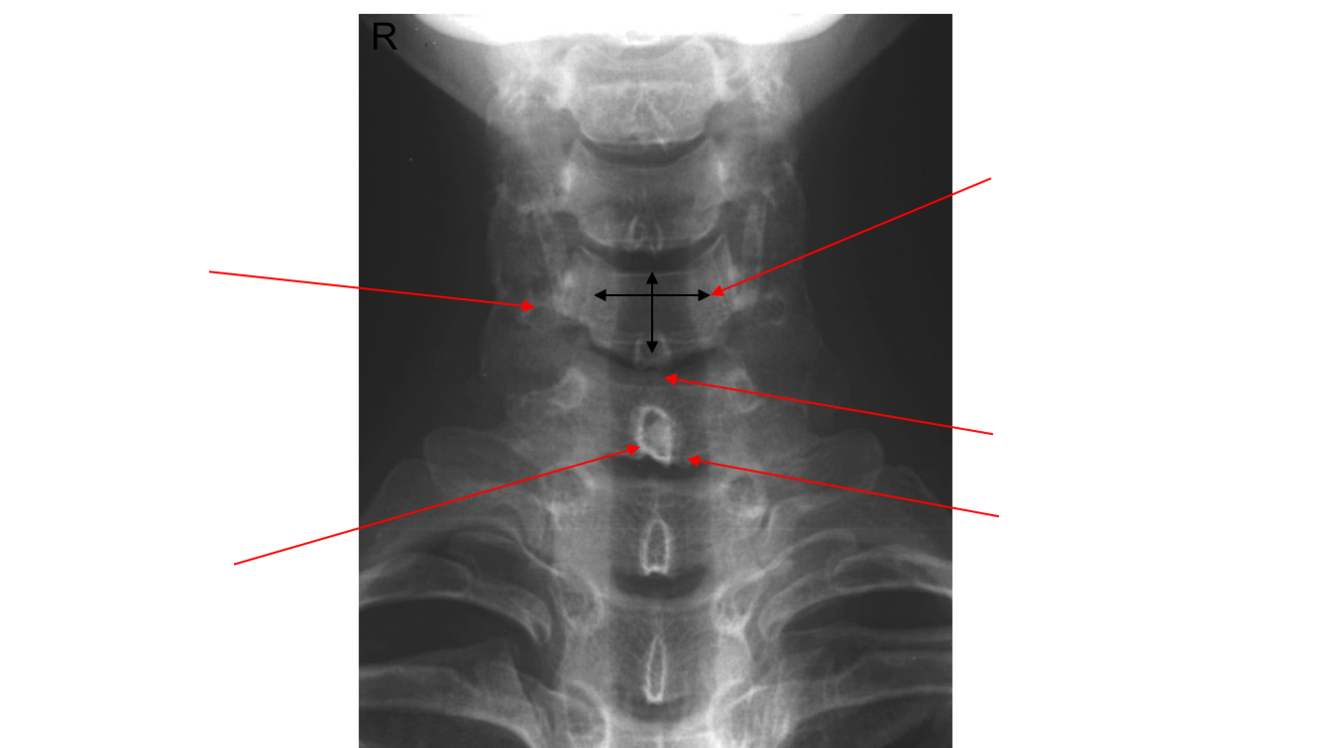

Label image